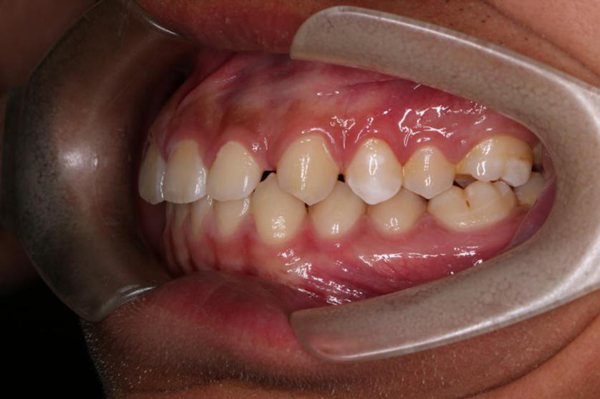

同样患有牙齿畸形的张俊斌也有了自己的小烦恼,牙齿稀疏让自己的牙缝看起来格外的大,有时露出浅浅的微笑都会让他人注意到自己的牙齿缺陷,这让正值青春期的张俊斌变得越来越沉闷、不爱说话,也开始抗拒与队友、教练之间的沟通交流,这不仅不利于整个团队的球技切磋、合作共进,也对张俊斌个人造成了极大的心理压力,影响其健康成长。

考虑到18岁的张俊斌对外貌美观有着一定的要求,在进行了详细、精密的口腔检查后,麦芽口腔硕博专家团为其量身定制了当下备受推崇的隐形正畸的矫牙方案。据悉,麦芽隐形矫治器采用无色透明的弹性高分子材料制成,近乎隐形,紧贴牙齿,佩戴舒适,几乎无异物感,可自由摘戴,丝毫不影响刷牙、饮食等日常生活,在悄无声息中就能完成牙齿矫正,备受孙杨、胡歌、小S等明星艺人、时尚潮流人士的青睐!